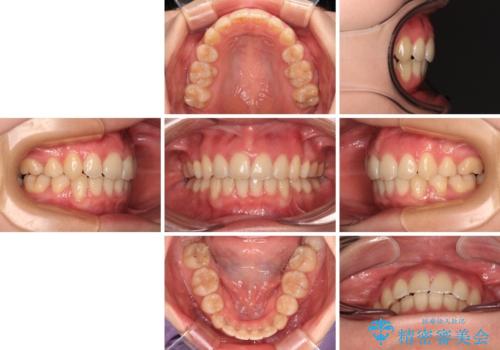

上下左右第一小臼歯4本を抜歯して、積極的に口元を引っ込めるよう、ワイヤー装置にて矯正治療を行うこととしました。

口の閉じにくさが改善され、横顔のシルエットも大幅に改善されました。